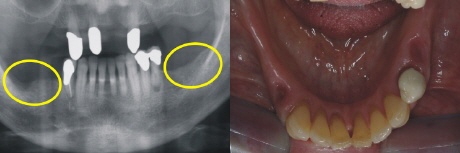

Ausgangssituation

Die Ausgangssituation zeigt eine beidseitige Freiendsituation (gelbe Kreise), die bislang mit einer herausnehmbaren Klammerprothese versorgt war. Die Patientin fühlte sich in ihrer Lebensqualität stark beeinträchtigt und wünschte einen festen Zahnersatz. Das Bild rechts zeigt in der Aufsicht die zahnlosen Kieferkammabschnitte.